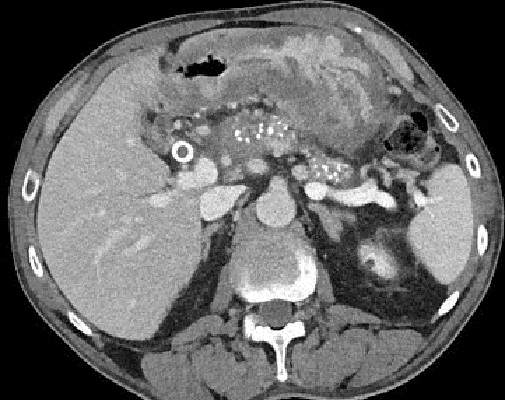

De meme cas en

coupe TDM axiale . Pancreas en volumineuse , a bord

irregulier en presence des calciofications et

depots hyperdence de tonalite calcique

parenchymateuse . Pancreatite chronique primitive |